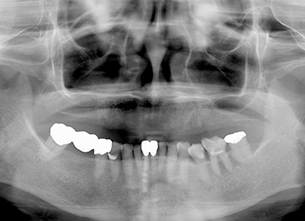

症例1 : 上下顎無菌顎症例

69歳、男性。

• 上顎は両側サイナスリフトと同時に即時荷重を行った。

• 下顎は抜歯即時埋入即時荷重を行った。

• 最終補綴物は、チタンのP.I.B.とM.B.のコンビネーションで修復した。

• 本症例の要旨は第39回日本口腔インプラント学会(大阪)にて症例報告した。